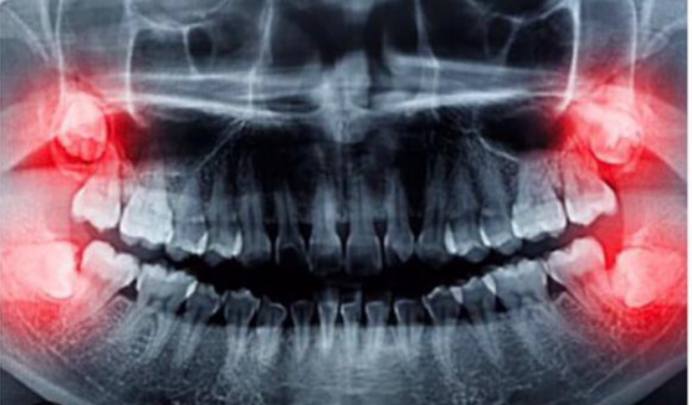

در واقع اگر دندان عقل شما مانند دندانهای دیگر رشد کرده باشد به روشهای متداول و عادی کشیده خواهد شد و نیازی به جراحی دندان عقل .نیست اما اگر دندان عقل به طور کامل از لثه خارج نشود و مقداری از آن در ا لته بماند، نیاز به جراحی دارد که به این دندان دندان عقل نیمه نهفته میگویند جراحی دندان عقل نیمه نهفته توسط دندانپزشک انجام میشود و ضروری است که هر چه سریعتر دندان عقل نیمه نهفته جراحی شود زیرا میتواند سبب التهاب لثه و عفونت آن شود.